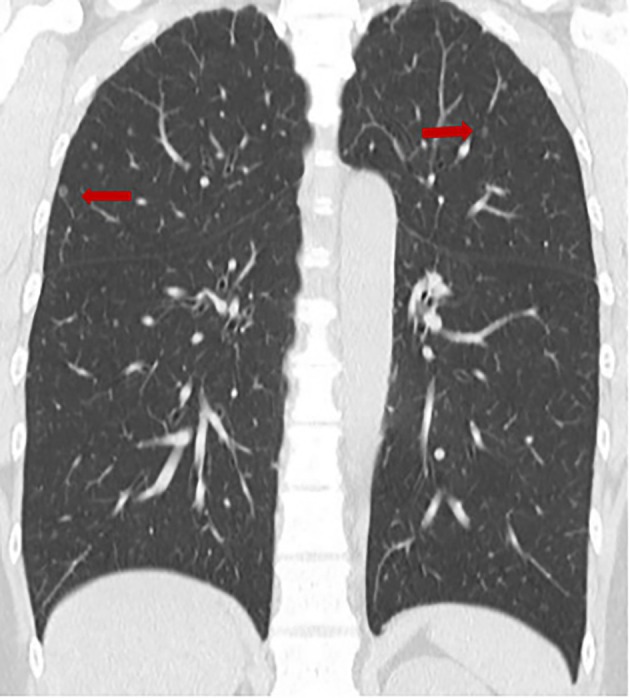

Diffuse pulmonary meningotheliomatosis (DPM) is a rare lung condition characterized by widespread meningothelial-like nodules and may radiologically mimic metastatic or granulomatous disease. We report a 2019-onset case of a 44-year-old woman with incidentally detected, bilateral 1-2-mm pulmonary micronodules on screening CT. Laboratory tests and pulmonary function were normal. Owing to the minute, peripheral distribution of the nodules, bronchoscopic biopsy was not feasible, and diagnostic video-assisted thoracoscopic wedge resection was undertaken. Histology showed spindle-to-ovoid cells in whorled arrangements without atypia or mitoses. Immunohistochemistry revealed diffuse vimentin positivity and negativity for epithelial and neuroendocrine markers (EMA, cytokeratin AE1/AE3, SMA, chromogranin). Postoperative brain MRI showed no intracranial lesion. The patient has remained asymptomatic without radiologic progression over 3 years. This case underscores DPM as an uncommon yet important differential diagnosis of diffuse pulmonary micronodules and highlights the need for histopathologic confirmation when bronchoscopic sampling is impracticable. Where available, PR and SSTR2A immunostains may further support the diagnosis.